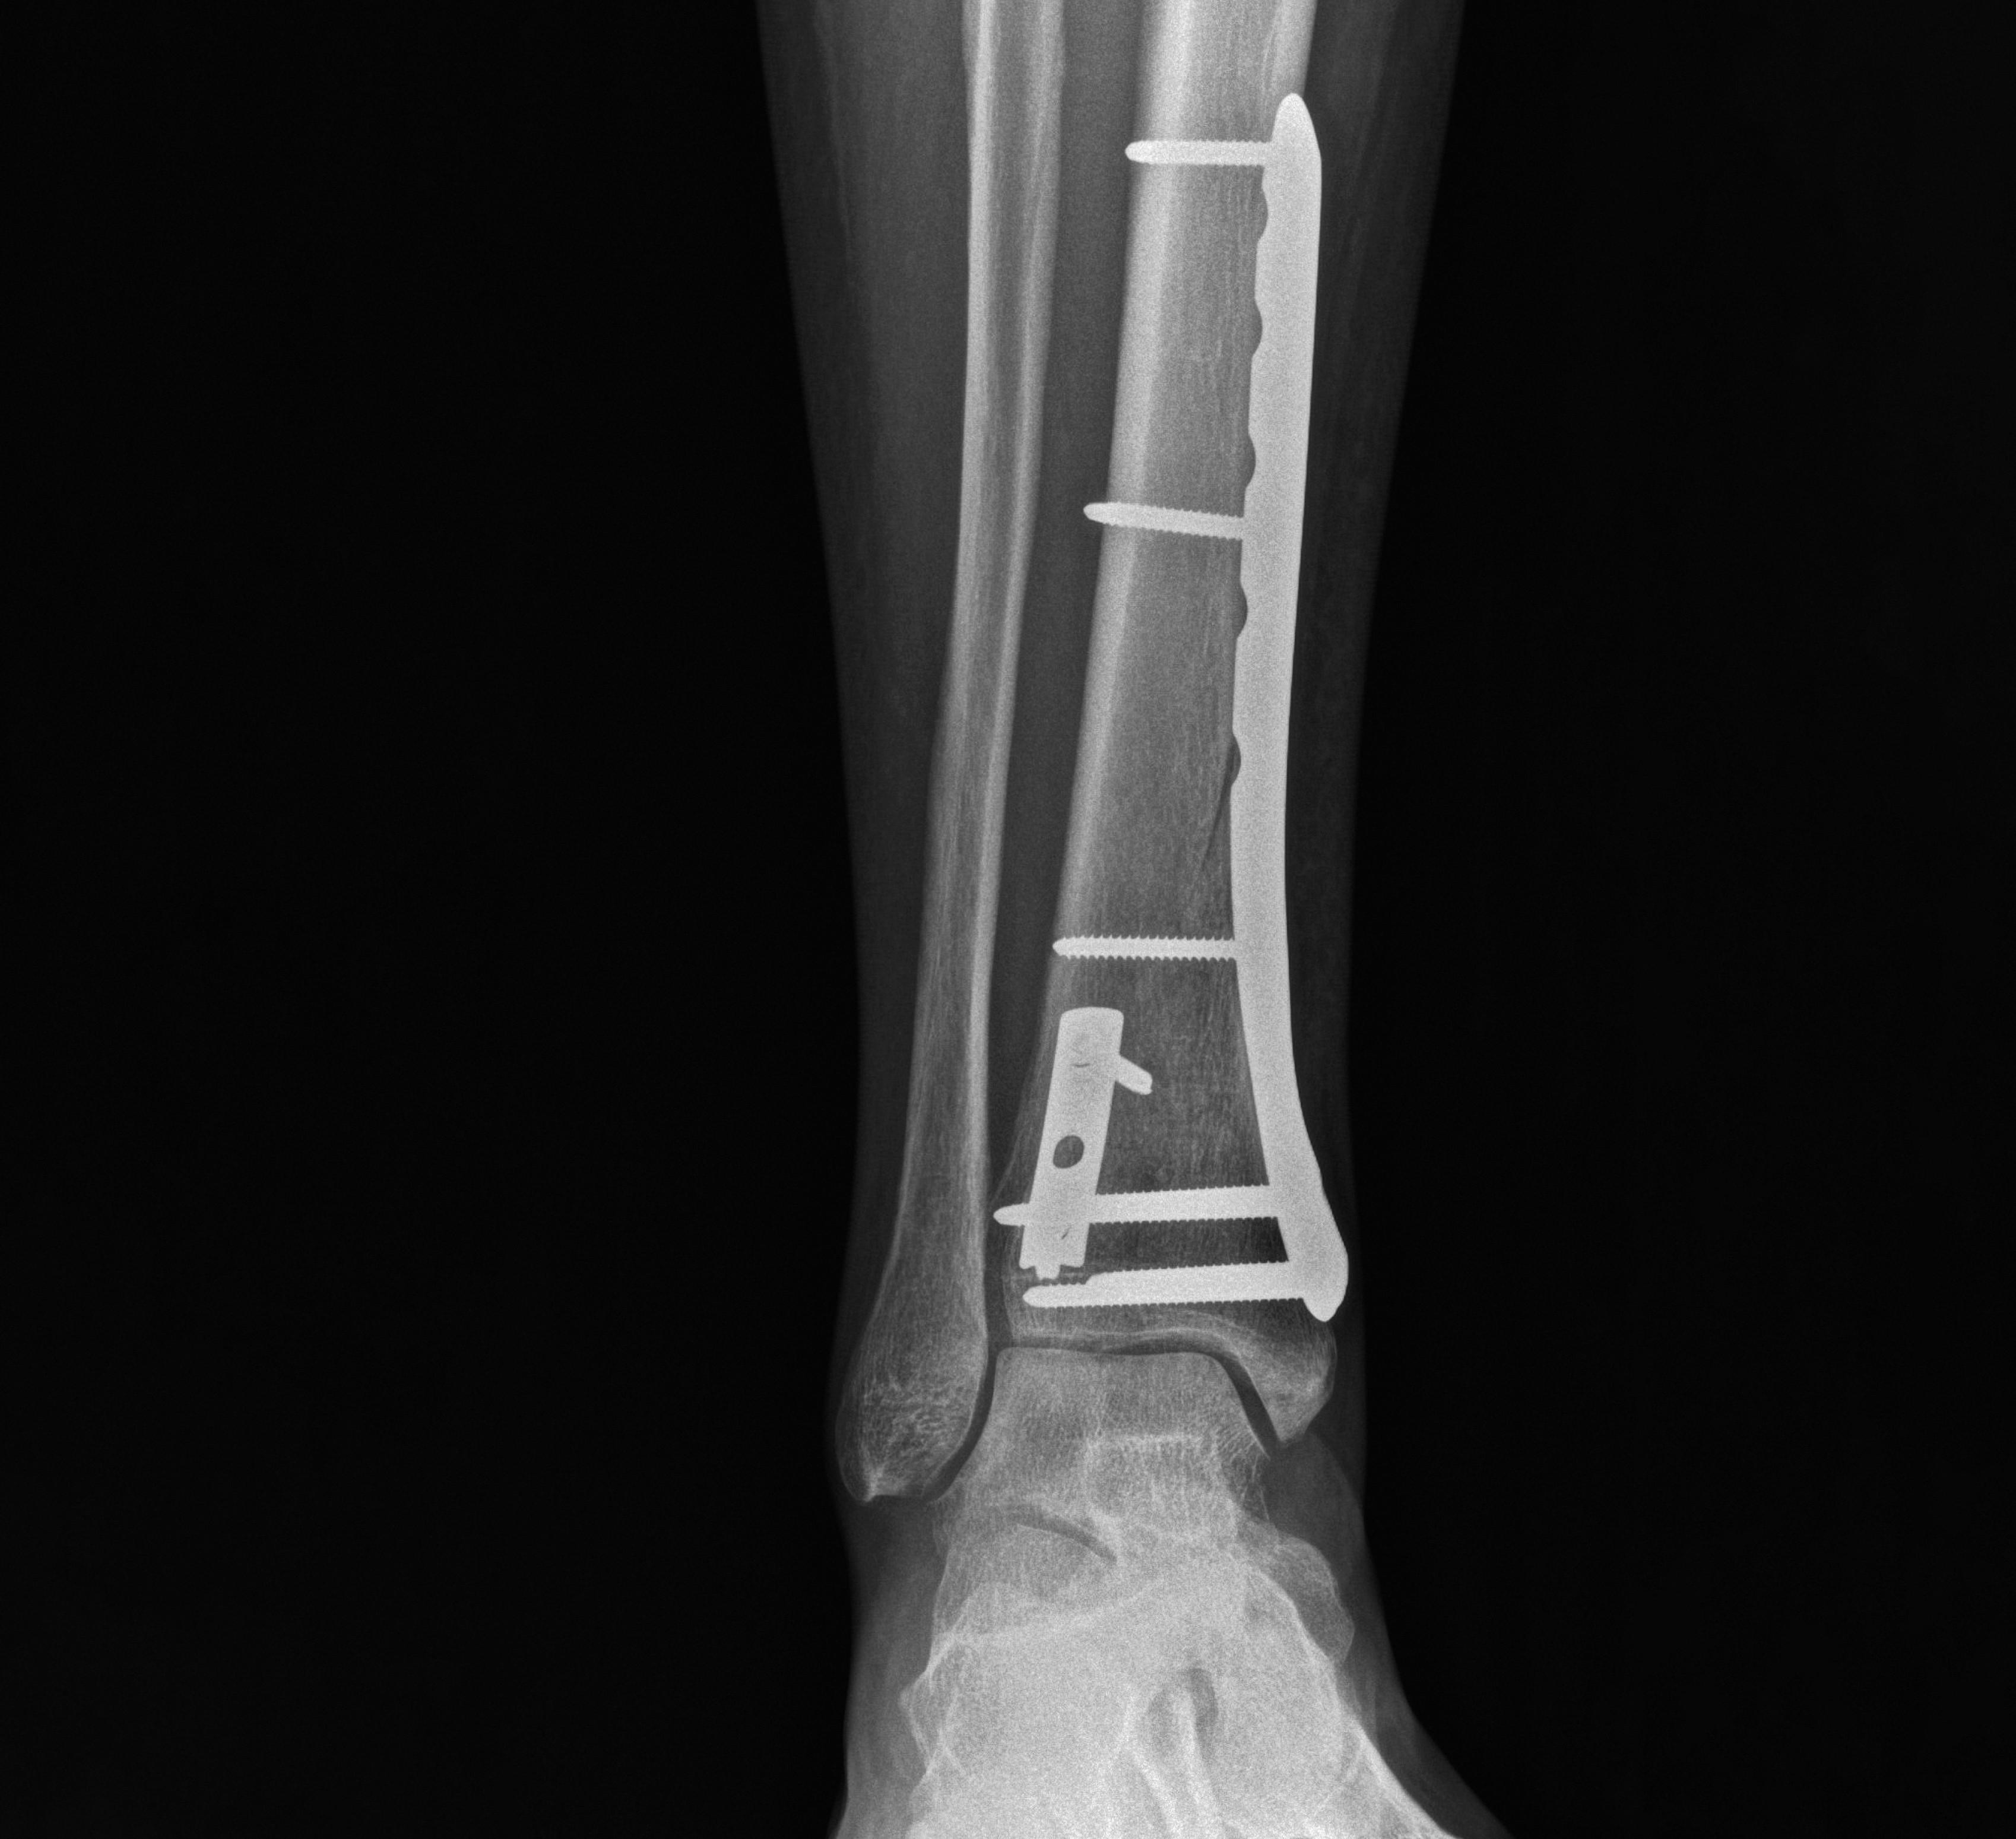

SALTI CLINICAL CASE: WORKSITE FALL RESULTING IN A PILON FRACTURE

We present a case of a healthy 50-year-old male bricklayer who sustained injuries in an accident at work. After falling approximately 2–3 meters on a construction site, he suffered a pilon fracture of the right tibia.

SALTI x-ray crop